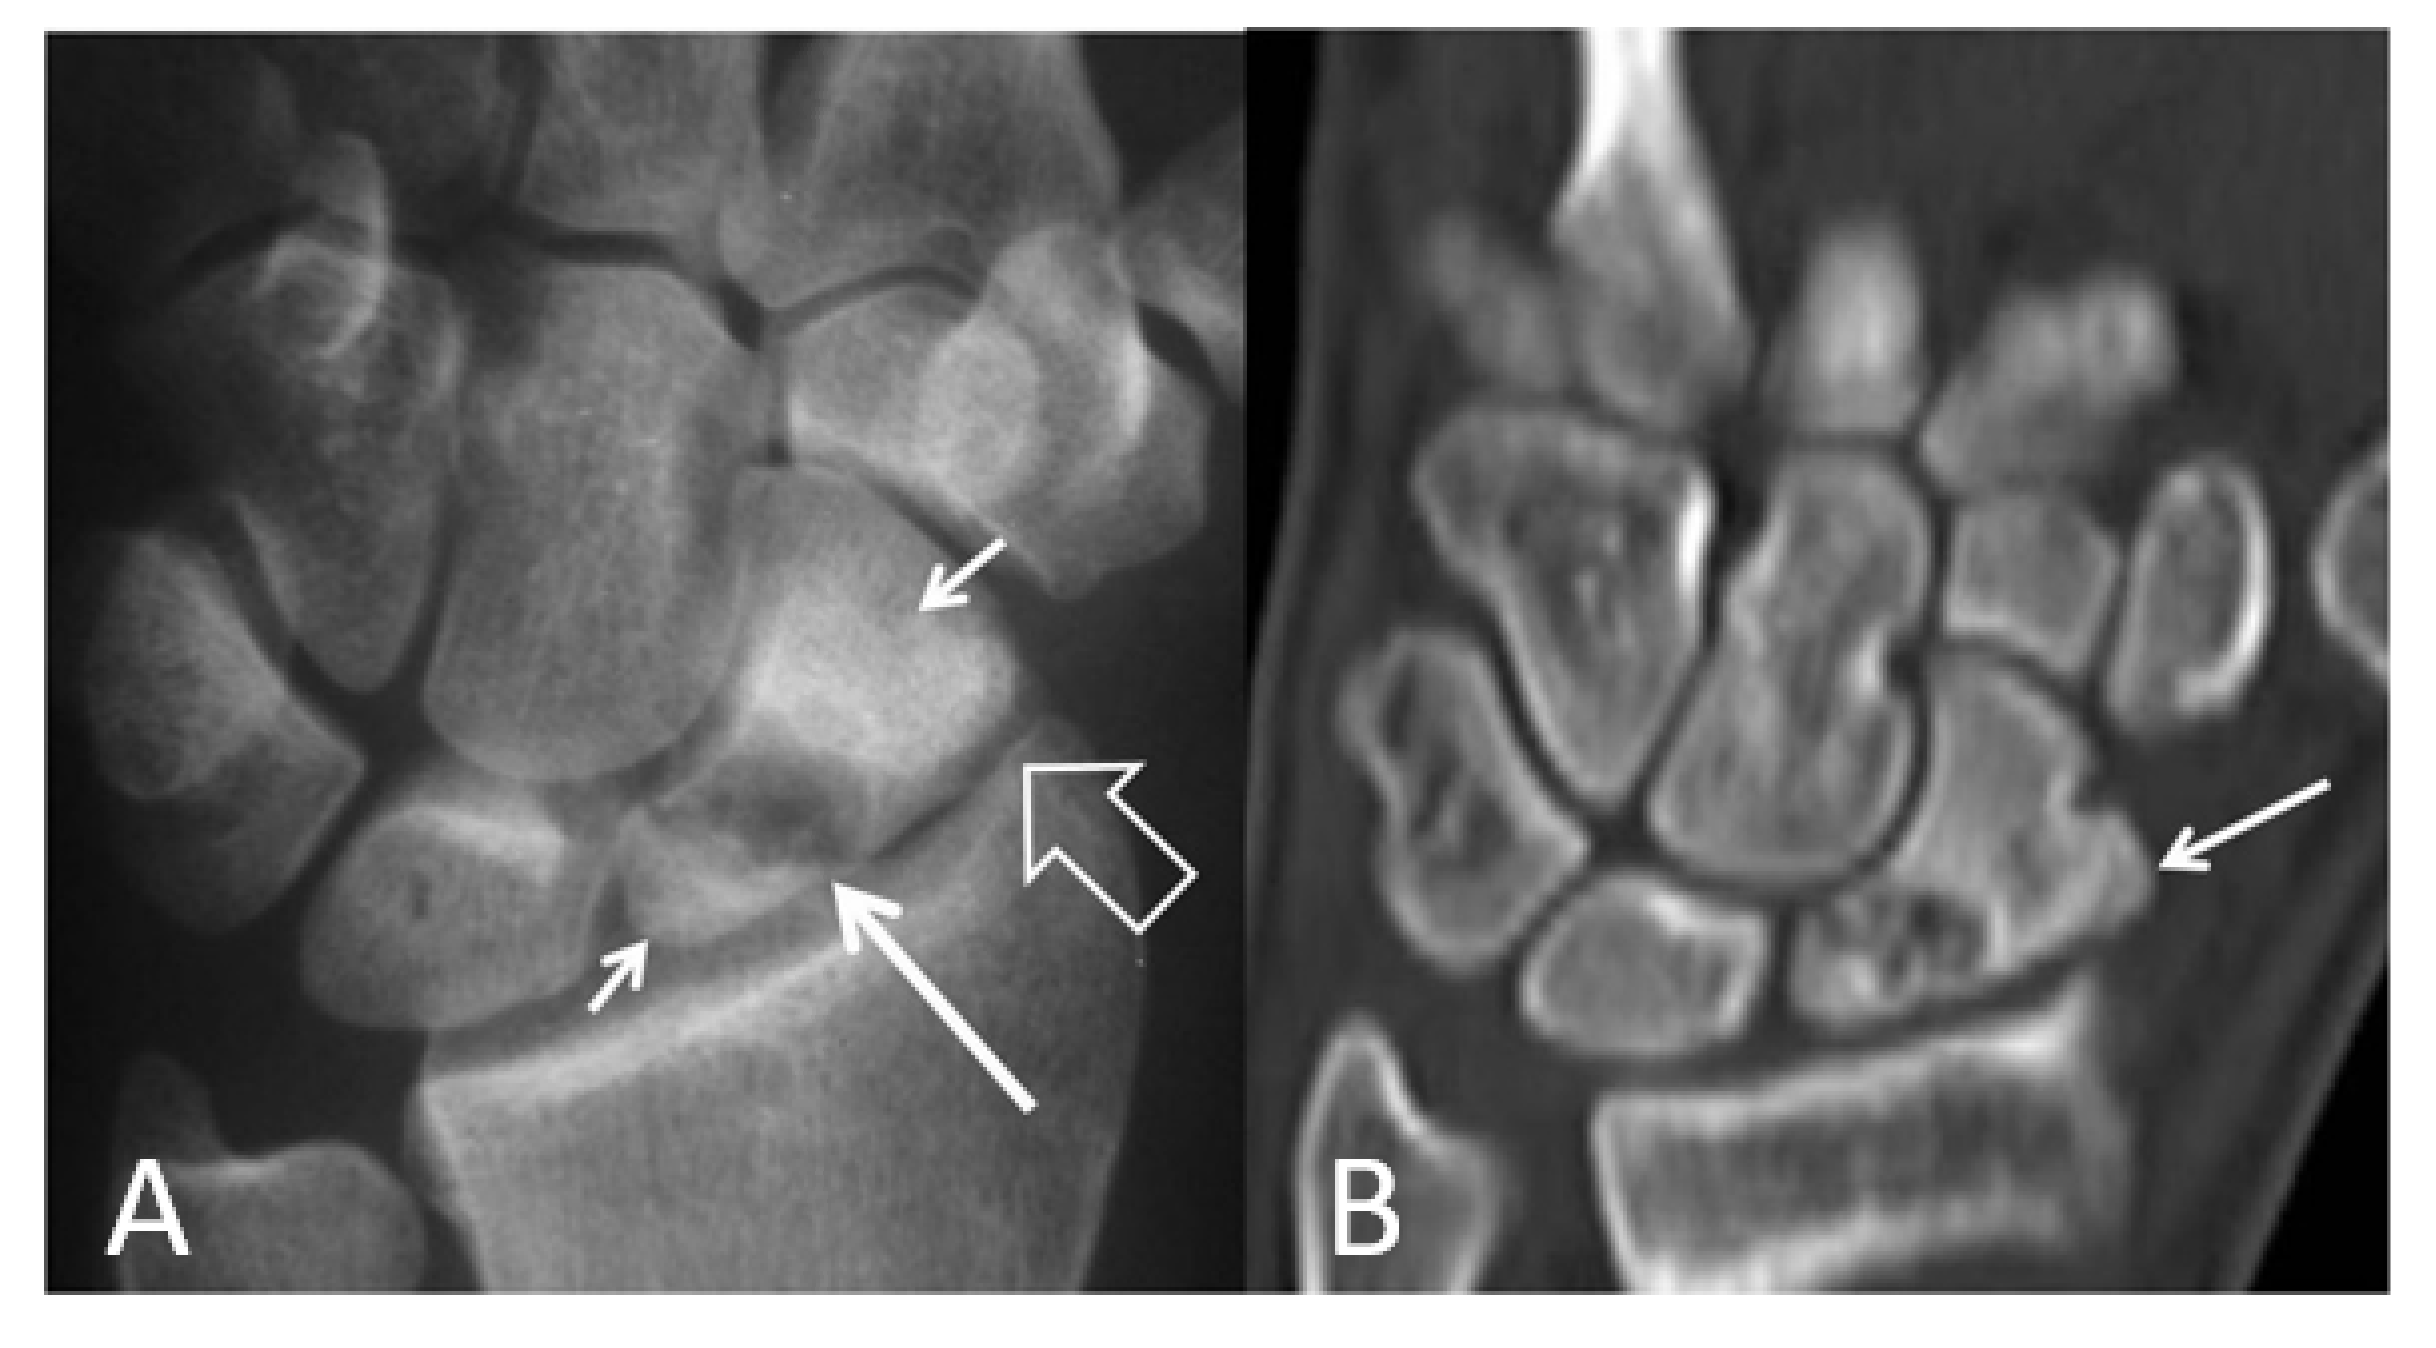

Figure 5.

Scaphoid pseudarthrosis and early SNAC wrist, in this 25-year-old male patient with an injury 4 years prior to current imaging. PA radiograph (A) showing the pseudarthrosis (long arrow), proximal and distal pole osteonecrosis (small arrows) and joint space narrowing at the most radial aspect of the radioscaphoid joint (open arrow). Coronal CT reconstruction (B), showing in addition osteophyte formation of the scaphoid bone (arrow).